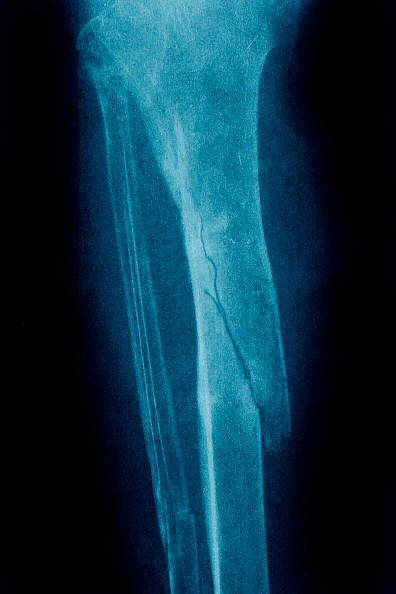

Los huesos de la mano, la tibia y el peroné (ambos en la pierna) y el fémur (hueso del muslo) son más propensos a curarse de forma poco adecuada.

Un estudio en el que se analizaron 166 fracturas de tibia tratadas quirúrgicamente estableció que el ejercicio temprano con pesas estaba relacionado con una curación más rápida, incluso en participantes que tenían fracturas de difícil mejoría.

La curación se definió como la capacidad de la persona para soportar peso sin dolor, además de contar con radiografías que mostraban que la fractura se había unido o reparado.